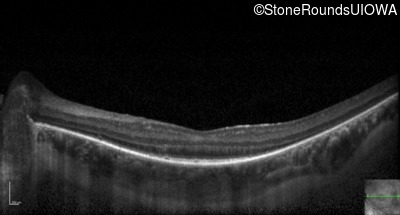

Optical Coherence Tomography - Right - 20/32 -1

Exemplar / OCT Stack

OCT Stack